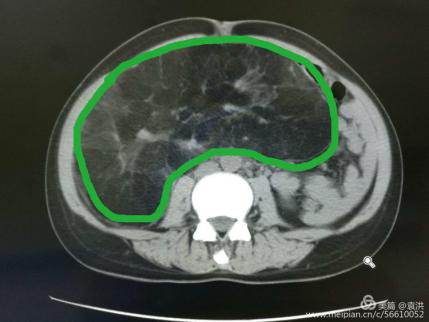

這一檢查讓婦科醫(yī)生也大吃一驚!醫(yī)生檢查時(shí)觸及腹部一硬質(zhì)包塊,無(wú)明顯邊界,上至劍突下,下至盆腔,兩側(cè)至腋中線,無(wú)壓痛,固定,說(shuō)明這包塊占據(jù)了患者整個(gè)腹腔,考慮來(lái)源于其它臟器,立即行全腹CT檢查??苫颊哂忻荛]空間綜合癥,一開(kāi)始拒絕CT檢查,醫(yī)生反復(fù)給患者做思想工作,并強(qiáng)調(diào)此項(xiàng)檢查的重要性,患者足足猶豫了兩天,才終于在醫(yī)護(hù)人員及家屬的鼓勵(lì)下順利完成了檢查。腹部CT提示,高度懷疑右腎有一顆脂肪肉瘤。

遂請(qǐng)泌尿外科會(huì)診協(xié)助診治,經(jīng)檢查,結(jié)合CT考慮腎周?chē)蚋鼓ず竽[瘤。最終診斷為:右腎巨大脂肪肉瘤。且腫瘤從腹腔延至盆腔,腹腔臟器受壓推移。醫(yī)生建議,子宮肌瘤多為良性,不影響生命,可暫緩手術(shù),但右腎巨大脂肪肉瘤必須盡快手術(shù)摘除。